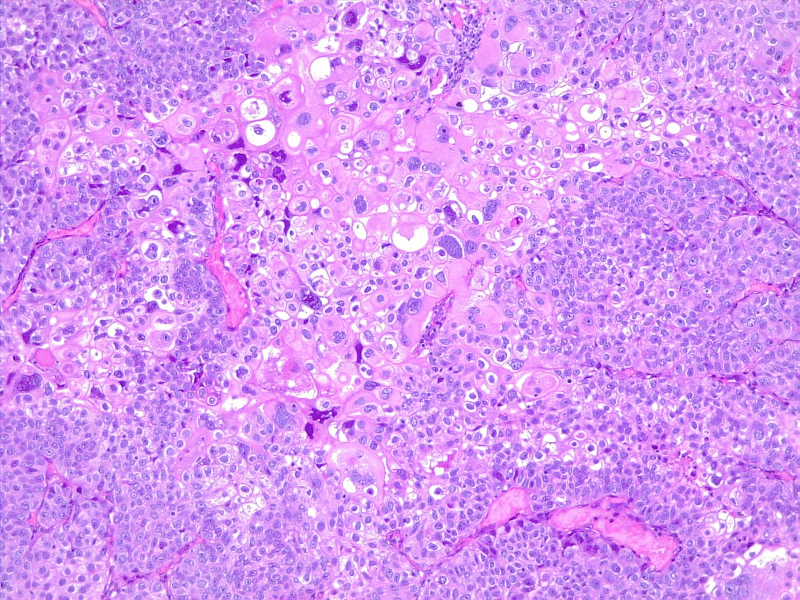

Poorly differentiated urothelial carcinoma, with metaplastic squamous appearance

圖3: 分化差的尿路上皮癌,具有化生性鱗狀外觀。10x,H/E。醫(yī)學(xué)博士 Fabiola Farci 供稿